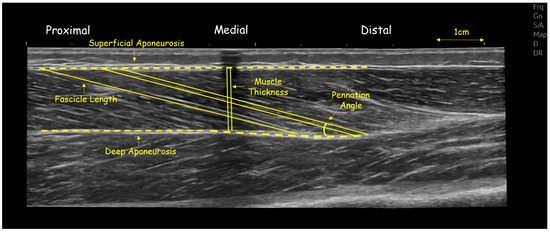

2.4. Ultrasonography